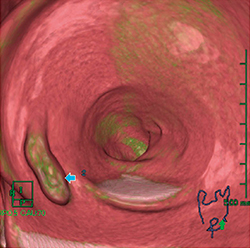

仮想内視鏡画像の魚眼モードでの解析は,半月ヒダの裏側まで観察可能で視認性が良好である。しかし,ポリープと残渣の識別は,完全に同期した2体位比較でなければ容易ではない。従来の2体位比較は,仮想内視鏡画像の方向が一定でなく,同一部位を観察していると認識することが難しかった。また,観察部位が肛門からの距離に応じて表示されるため,拡張度の違いにより観察部位のズレが生じた。そのため,画像解析に当たっては,クレンジング処理をOFFにした仮想内視鏡MPR断面にて背臥位と腹臥位を個別に解析した後,2体位比較で隆起部位の解析を行わなければならず,煩雑であった。

当院では,独自にカラーマップを作成し,ポリープを緑色,タギング残渣を白色とした。このカラーマップにより,視覚的にタギング残渣とポリープが識別可能となった。

図7 ポリープと残渣を色分けしたカラーマップ

緑色はポリープのCT値0~80HUを,白色はCT値100HU以上を示す。